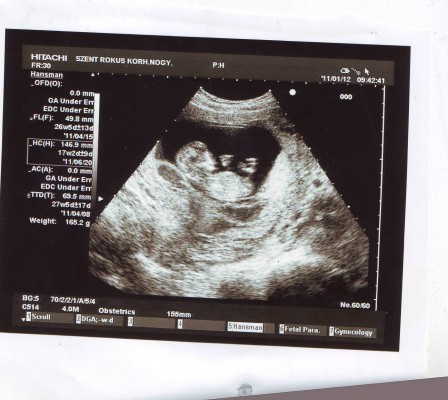

Kép

Na ő itt Ő:D

12hét +5 nap:D